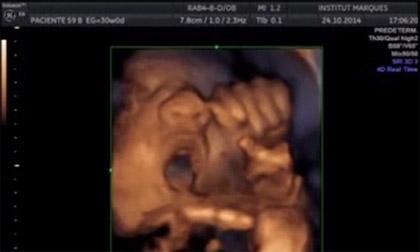

Đó là nghiên cứu được thực hiện và công bố bởi các nhà khoa học tại trung tâm nghiên cứu Institut Marques ở Barcelona, Tây Ban Nha. Cụ thể thai nhikhi 16 tuần tuổi đã có khả năng phát hiện âm thanh, phản ứng lại bằng cách cử động miệng và lưỡi.

Nhóm nghiên cứu đã sử dụng một thiết bị có tên là Babypod nhằm giúp các bà mẹ kích thích kỹ năng giao tiếp cho thai nhi trước khi chúng được sinh ra.

Thai nhi 16 tuần tuổi đã biết hát theo nhạc.

Thí nghiệm được thực hiện trên phụ nữ mang thai giữa tuần thứ 14 và thứ 39 của thai kỳ. Phản ứng của thai nhi trong khi cho chúng nghe nhạc được ghi lại bằng máy siêu âm.

Trước khi nghe nhạc có khoảng 45% số thai nhi cử động đầu và chân tay, trong khi 30% chuyển động miệng hoặc lưỡi, và 10% không biểu hiện gì.

Khi tiếp xúc với âm thanh phát ra thông qua thiết bị babypod được đặt vào âm đạo, 87% thai nhi phản ứng, cử động đầu và chân tay, kèm với đó là miệng và lưỡi chúng chuyển động. Khi âm nhạc dừng thì chúng cũng dừng theo.

Có đến 50% thai nhi phản ứng rất rõ rệt, hàm và lưỡi chuyển động mạnh như đang cố nói hoặc hát theo.

Còn khi đặt babypod trên bụng mẹ thì không có quá nhiều thay đổi trên khuôn mặt của thai nhi. Những thai nhi song sinh có những biểu hiện tương tự nhau.